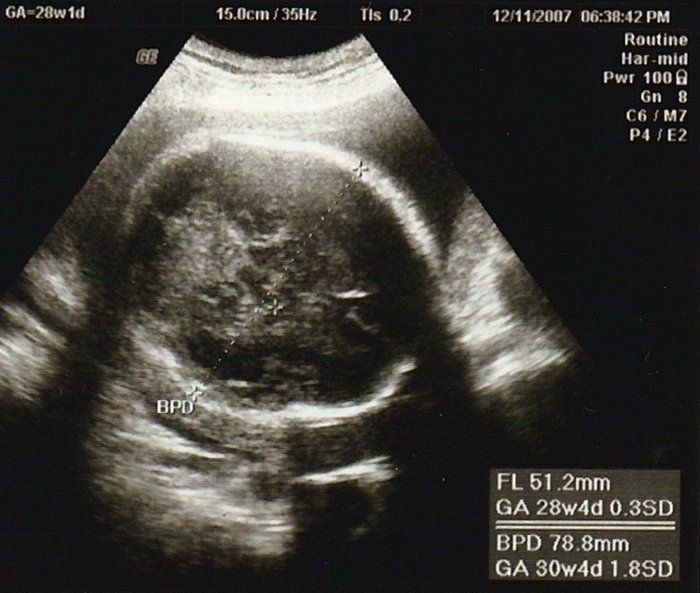

小吉さんの妊娠28週目のエコー写真

赤ちゃんの頭の大きさ(BPD)とお腹周り(AC)を測りました。赤ちゃんの成長は順調そのものでしたが、血液検査の結果で貧血の治療が必要となり、服薬はもちろんのこと、点滴のため週2回程度の病院通いが始まりました。